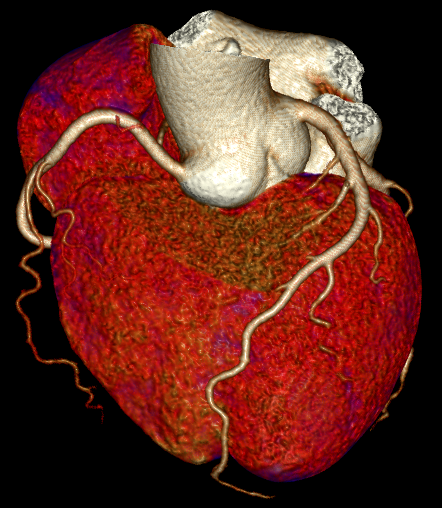

图三:通过ROI勾画,可提供散点图、直方图以及能谱曲线分析

能谱成像技术可分析病灶组织成分与特性,为肿瘤同源性鉴别等提供常规CT无法获取的关键信息,为医生提供更丰富的诊断依据。